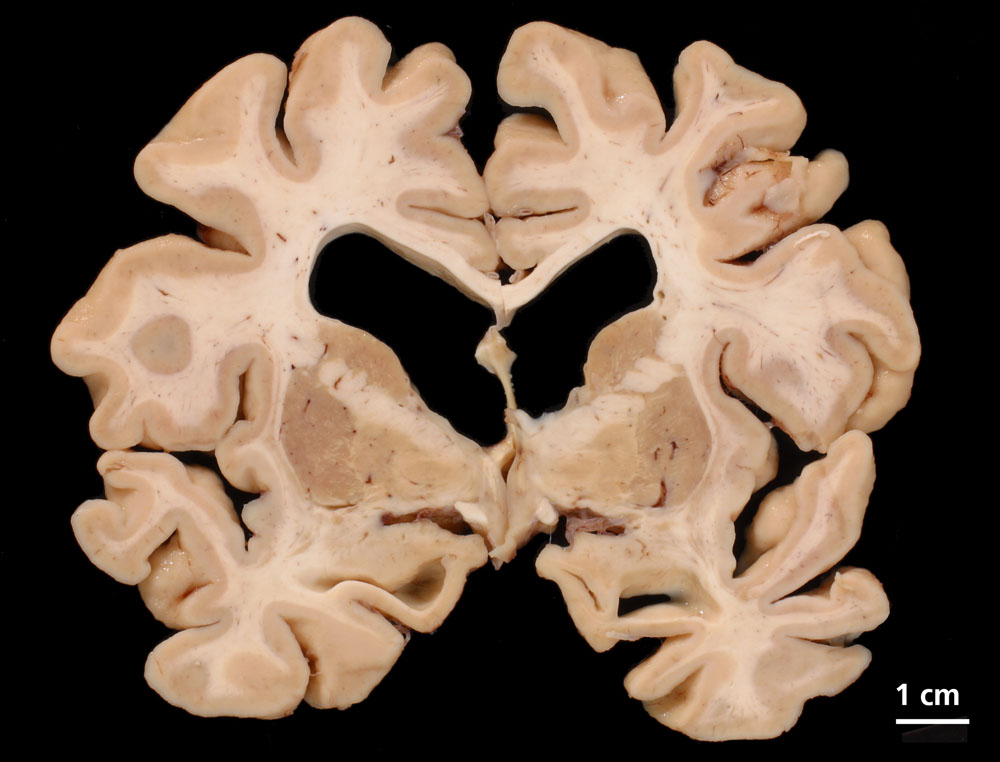

Gehirne von Alzheimer Patienten sind makroskopisch durch eine kortikale Atrophie (vor allem temporo-parietal) charakterisiert. Weiter findet sich meist eine deutliche Atrophie von Hippocampi und Mandelkernen. Diese geht einher mit einem Hydrocephalus internus (e vacuo), wobei vor allem die Temporalhörner der Seitenventrikel betroffen sind.

Die wichtigsten mikroskopischen Veränderungen sind die senilen Plaques und die Alzheimer Fibrillenveränderungen. Wesentlicher Bestandteil der senilen Plaques ist das A-beta Peptid, ein Spaltprodukt des Amyloidvorläuferproteins. Immunhistochemisch lassen sich verschiedene Plaqueformen unterscheiden, wobei der Nachweis von neuritischen Plaques entscheidend ist. Neuritische Plaques bestehen aus einem zentralen Amyloidkern, der von dystrophen neuritischen Fortsätzen umgeben ist. In der Umgebung der Plaques findet sich meist eine Mikrogliaproliferation und –aktivierung. Es besteht keine gute Korrelation zwischen der Plaquedichte im Kortex und dem Grad der klinisch erkennbaren Demenz. Die Alzheimerfibrillen (=Tangles) sind intraneuronale Einschlüsse, die aus Aggregaten des Mikrotubulus-assoziierten Proteins Tau in hyperphosphorylierter Form bestehen. Ausserdem finden sich Tau-Ablagerungen in Neuriten (=Neuropilfäden=neuropil threads). Im Gegensatz zu den Plaques korrelieren Dichte und Verteilungsmuster von Alzheimerfibrillen und Neuropilfäden wesentlich besser mit dem klinischen Schweregrad der neuropsychologischen Beeinträchtigung. Das Auftreten und das Verteilungsmuster von Alzheimerfibrillen und Neuropilfäden verläuft nach einem stereotypen Muster, das für die Stadieneinteilung I bis VI nach Braak benutzt wird. Braak unterscheidet ein entorhinales Stadium (I/II), ein limbisches Stadium (III/IV) und ein neokortikales Stadium (V/VI). Beim Nachweis von zahlreichen neuritischen Plaques und Neurofibrillenveränderungen entsprechend einem Braak Stadium V oder VI besteht eine hohe Wahrscheinlichkeit, dass die Demenz durch Morbus Alzheimer verursacht wurde. Die Fibrillenveränderungen lassen sich in der Gallyas-Färbung besonders gut darstellen (Versilberung).